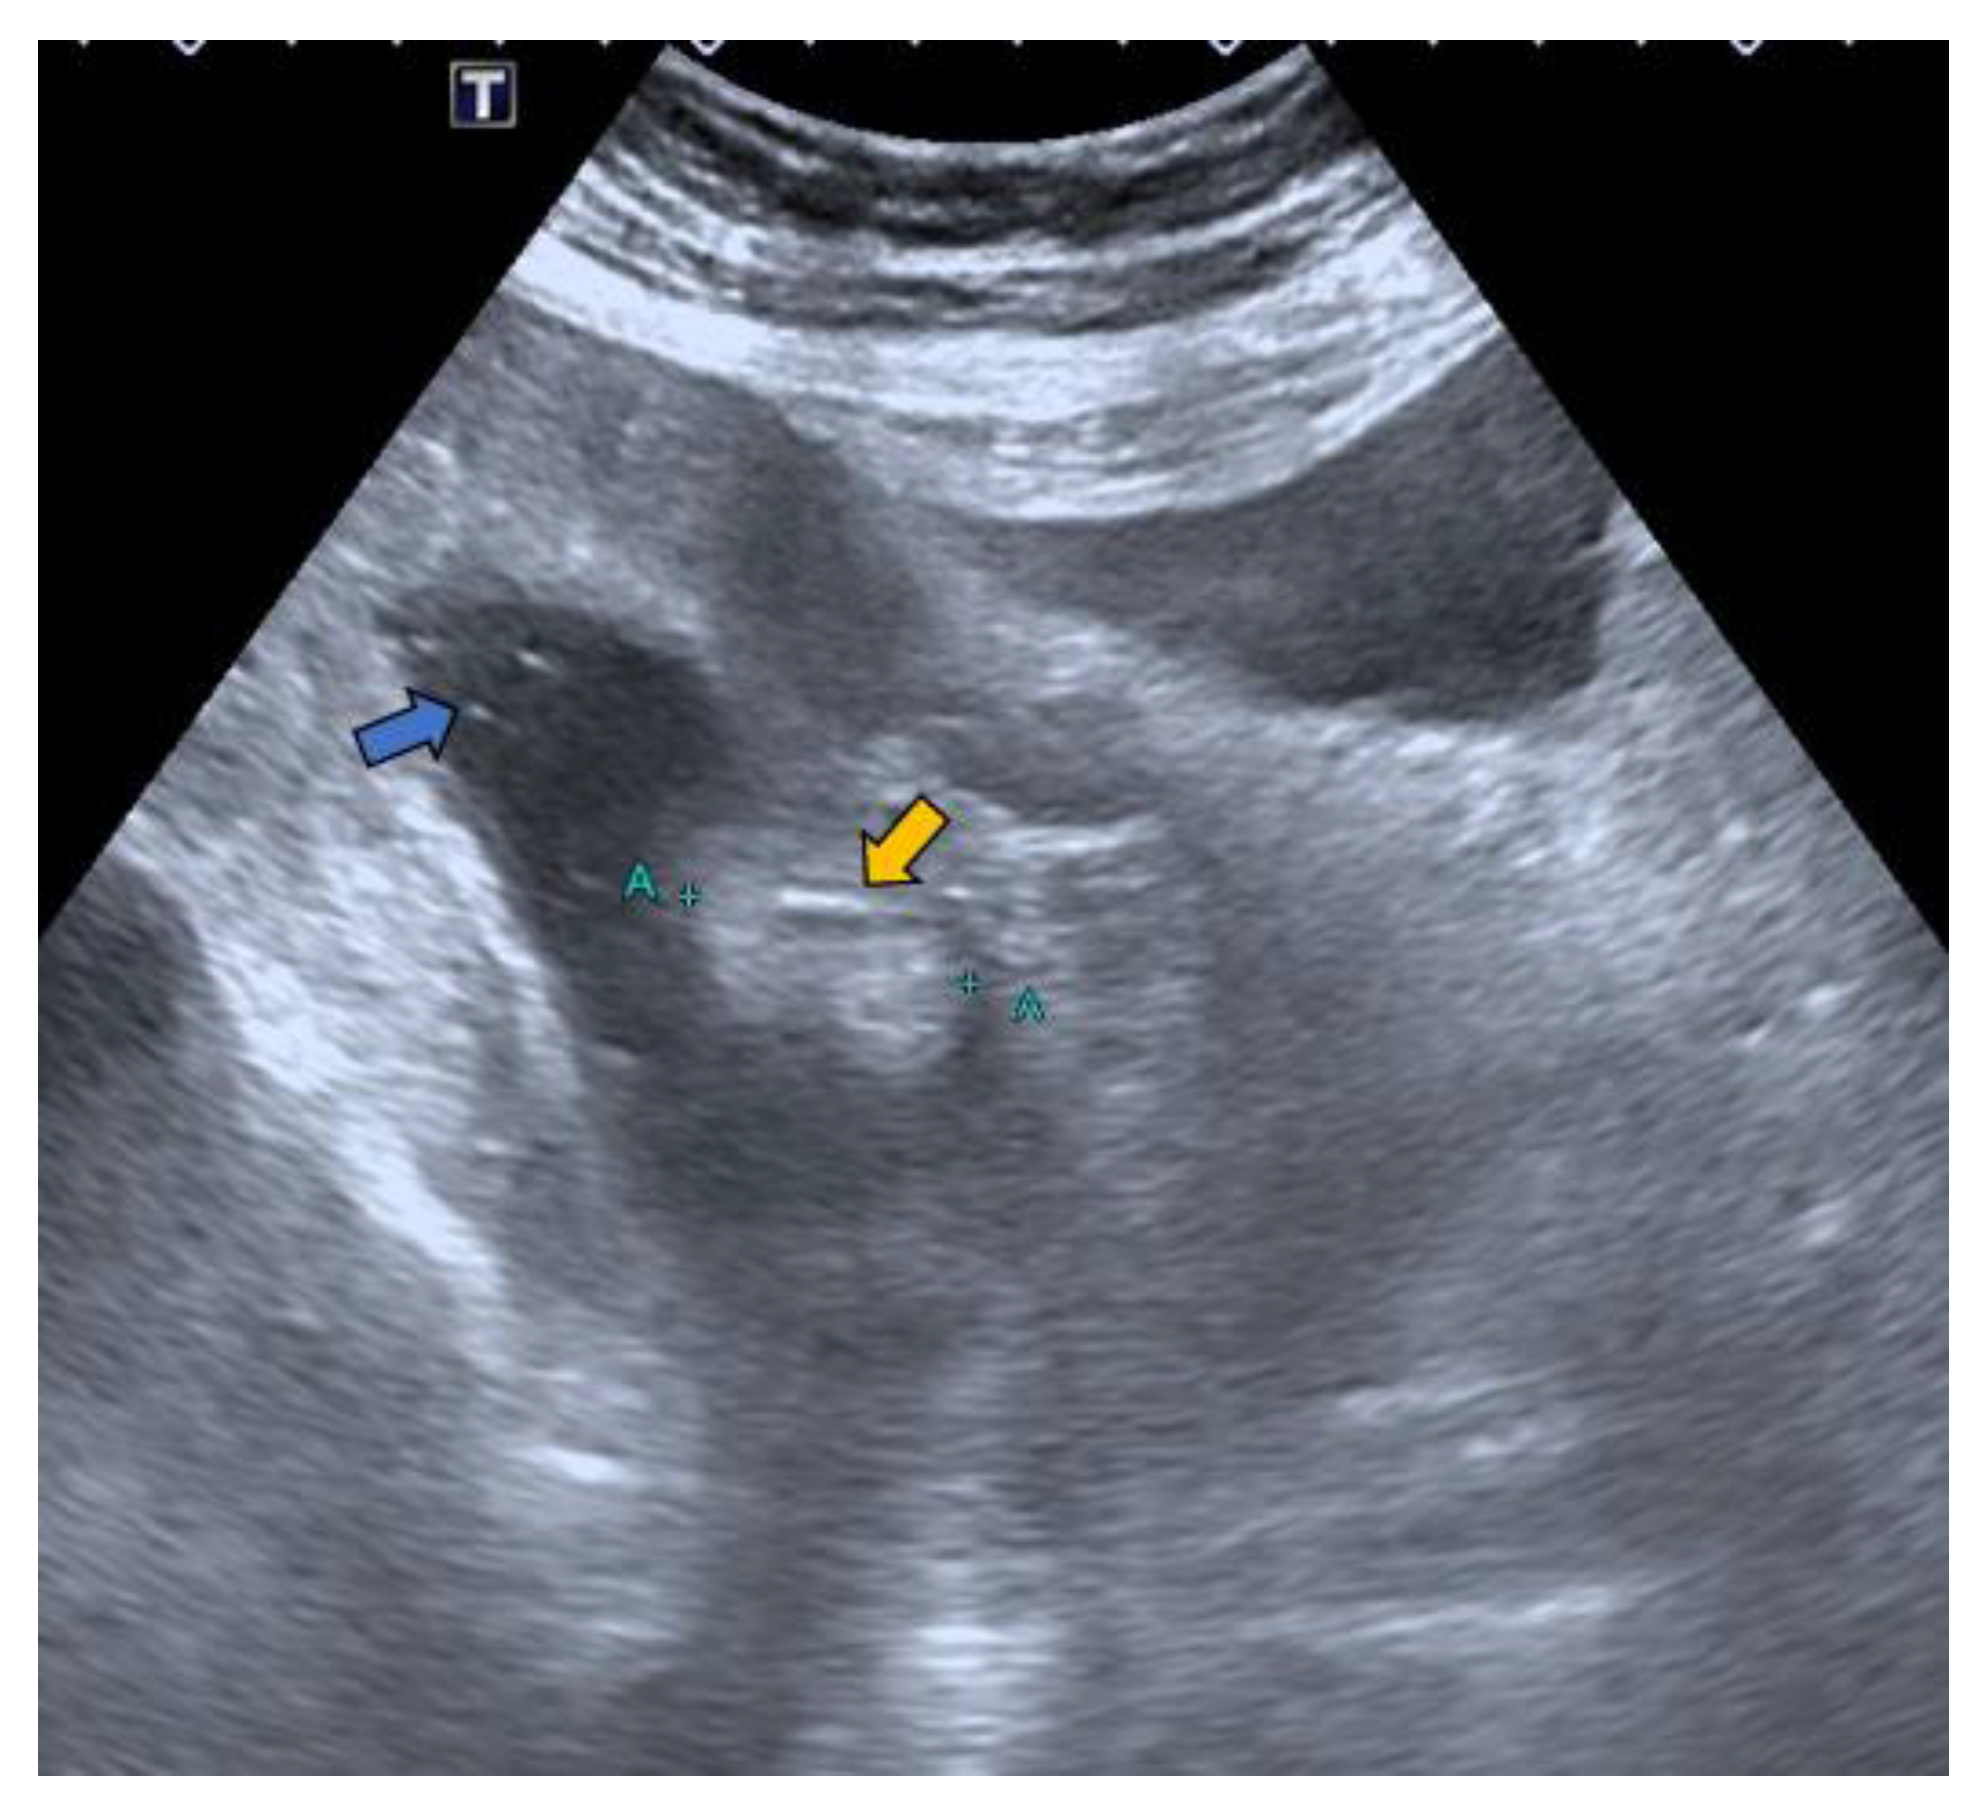

Figure 3.

Hydrocolonic sonography without cleaning preparation. The lipoma between the blue marks (A +, + A) is seen as a hyperechoic image (yellow arrow) projecting into the lumen of the cecum. Faecal remains are observed floating as hyperechoic dotted images in the lumen of the co-lon distended by the serum (blue arrow).